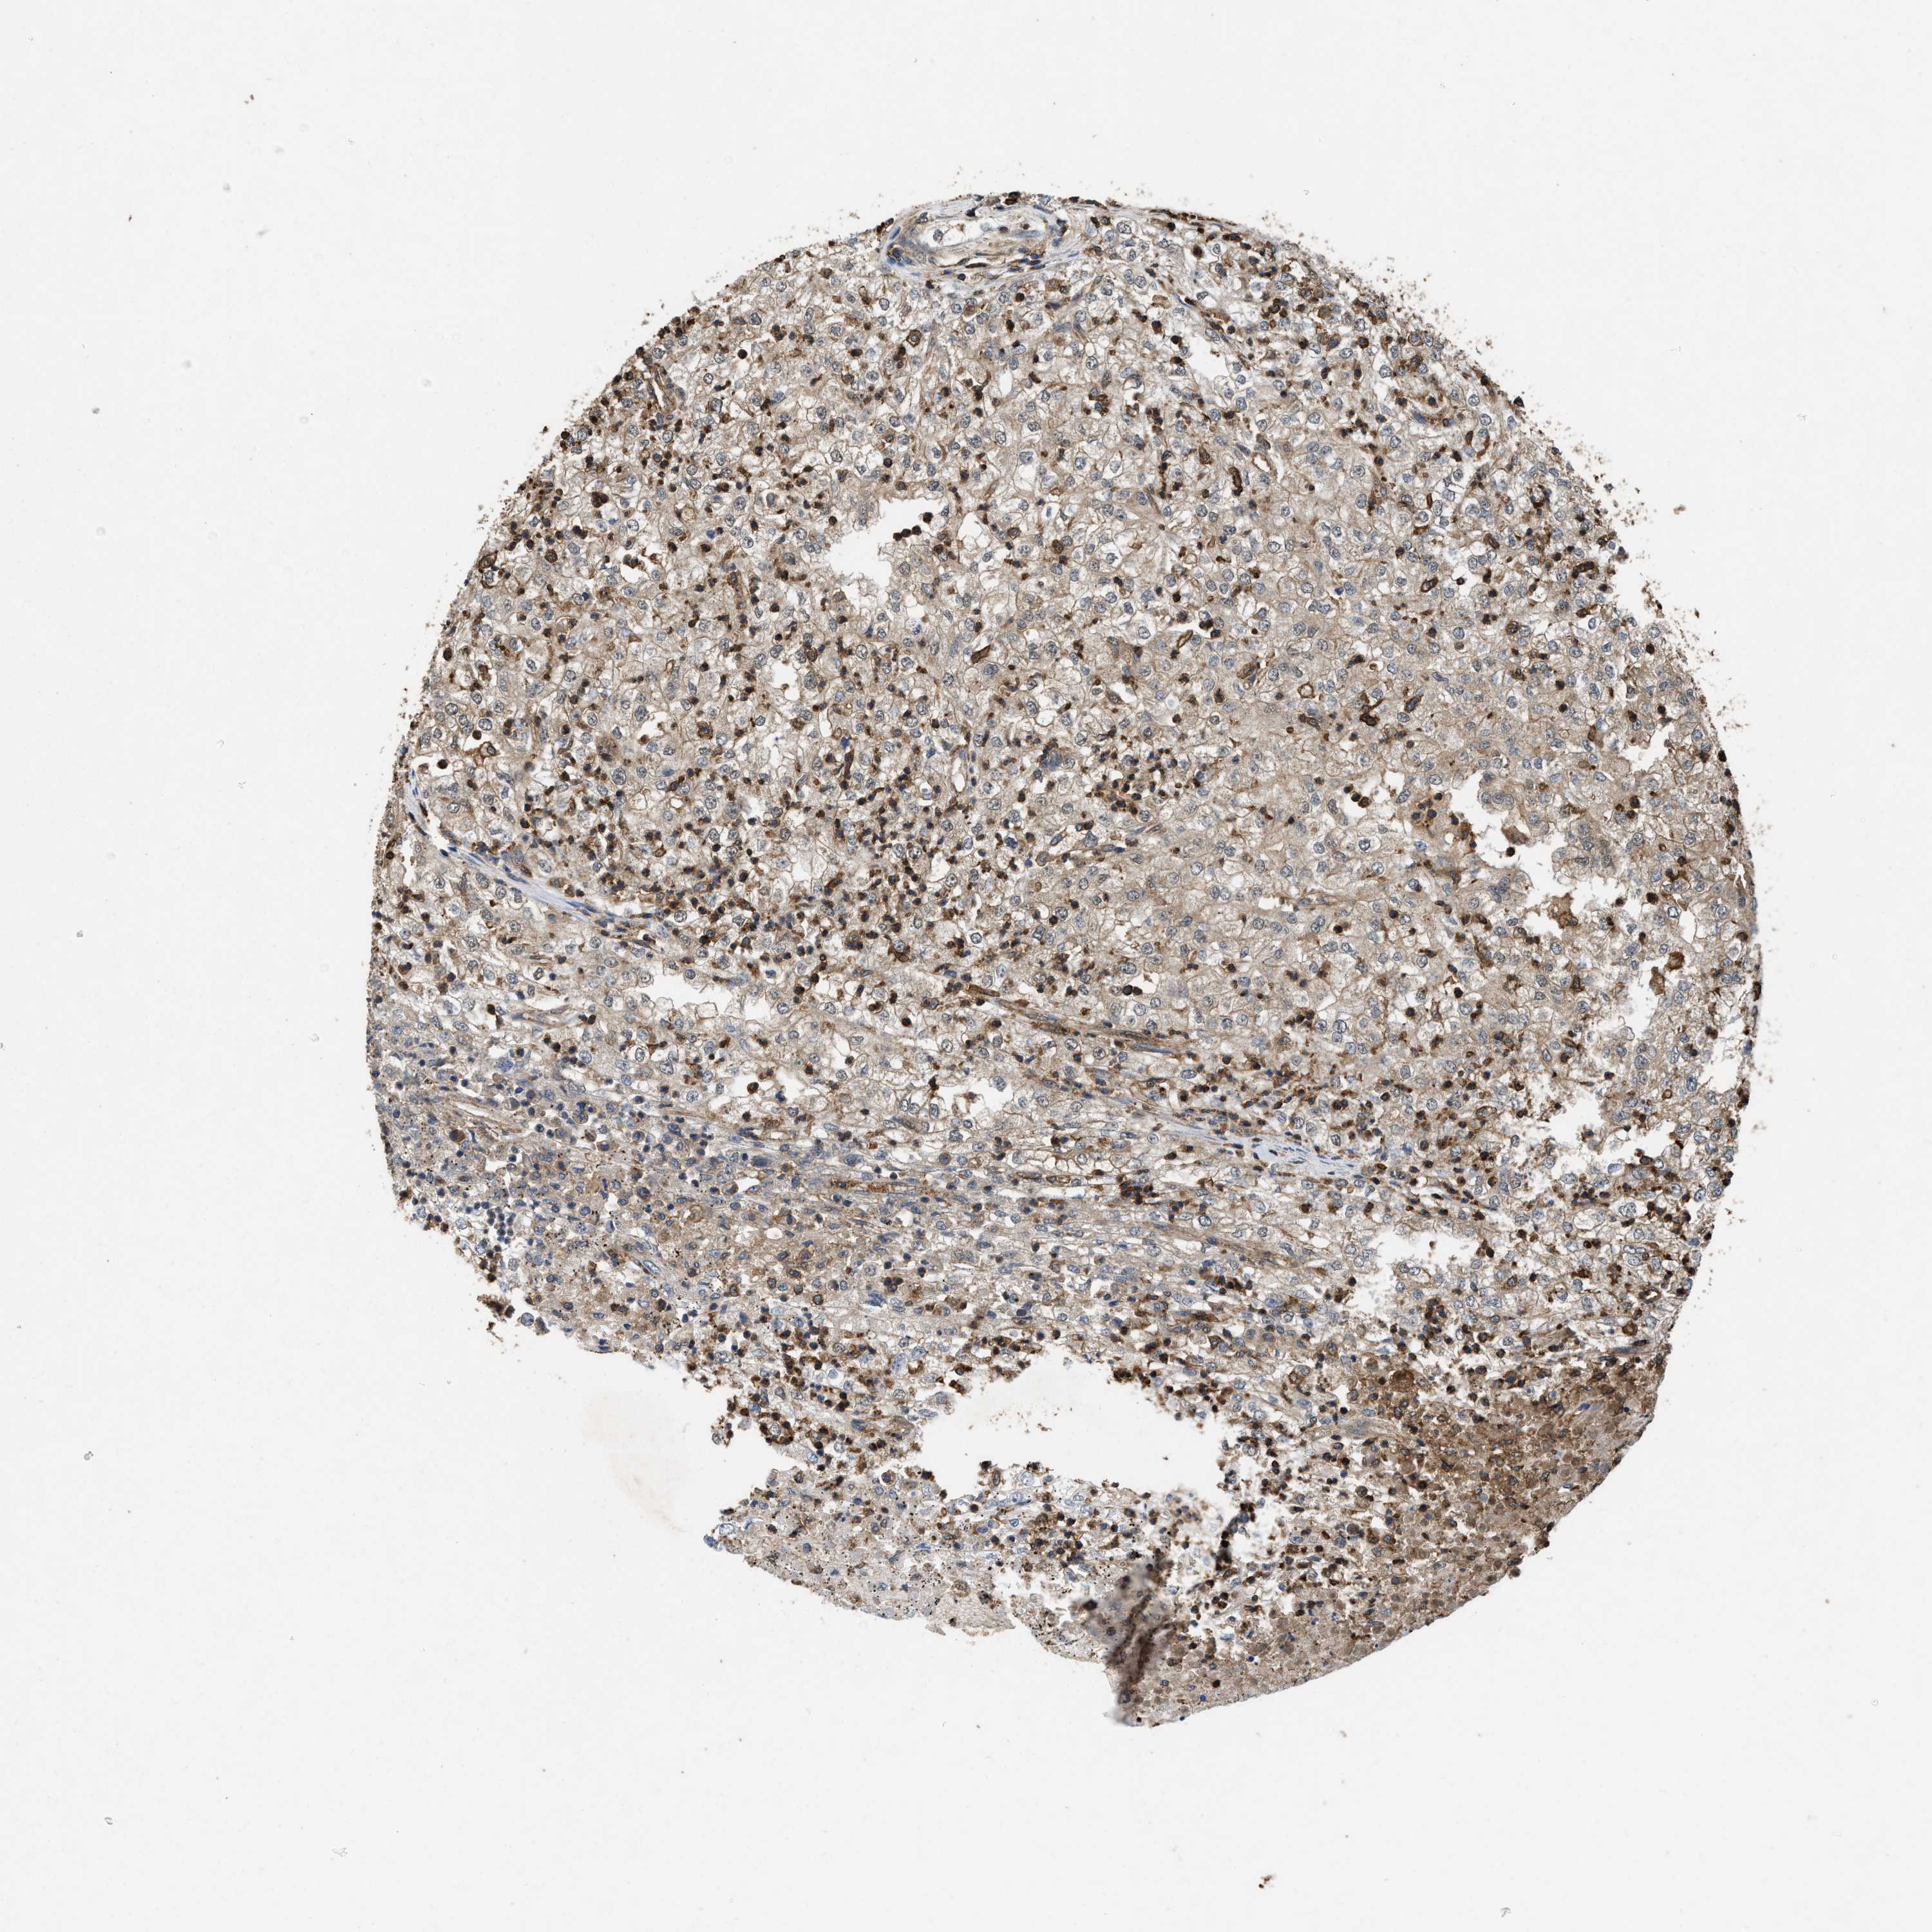

CANCER RENAL CANCER Show tissue menu

KICH TCGA KIRC TCGA KIRC VALIDATION KIRP TCGA PROTEIN RCC CPTAC PROTEIN EXPRESSION

KIDNEY RENAL CLEAR CELL CARCINOMA (VALIDATION) - Interactive survival scatter ploti

LINGO2 is not prognostic in Kidney Renal Clear Cell Carcinoma (validation)